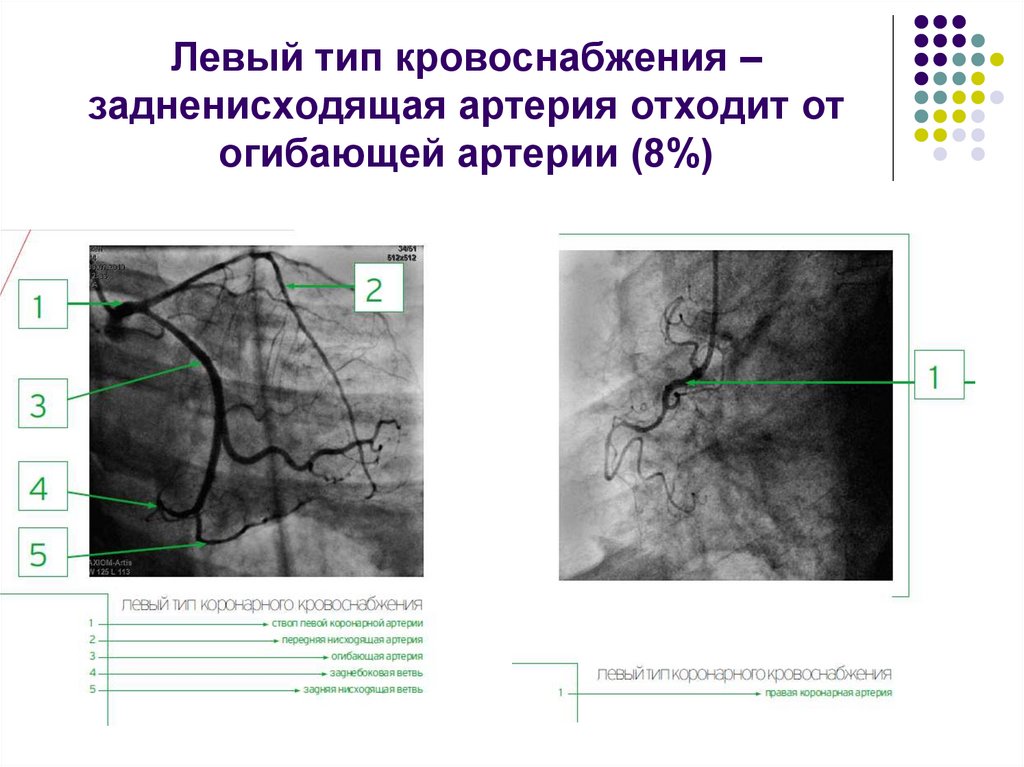

Особенности и диагностика левостороннего кровотока